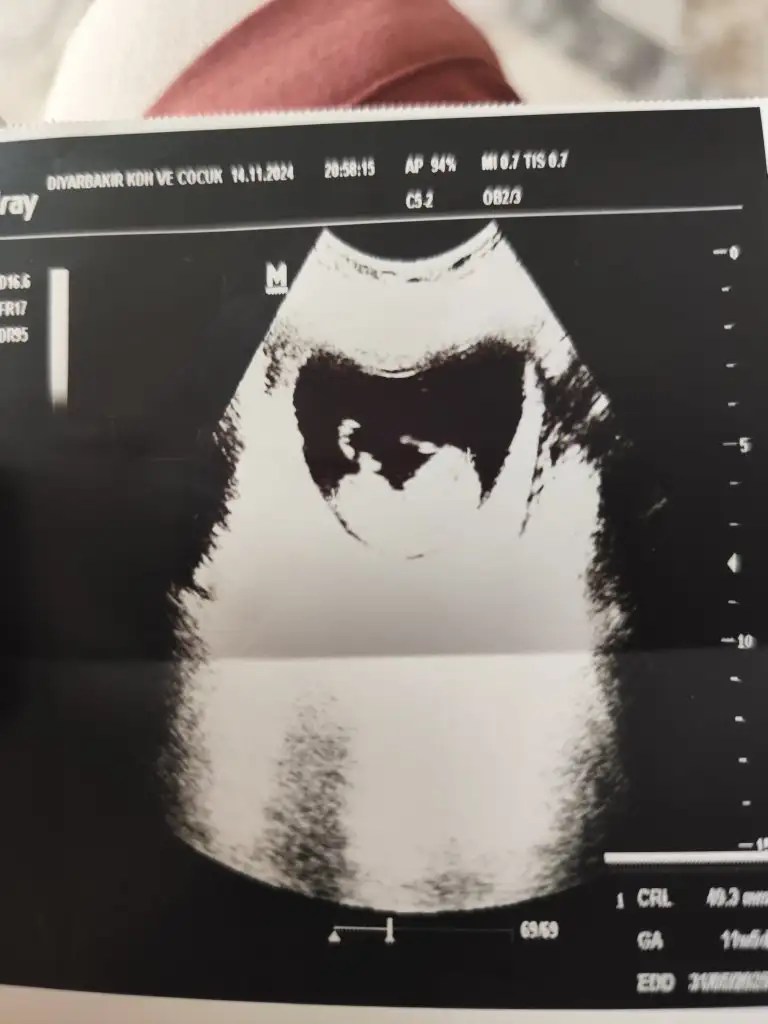

Merhaba benim bebeğimi de tahmin edermisiniz

Sata göre 11 haftalık

• 1000023488.webp

1000023488.webp

21,3 KB · Görüntüleme: 94